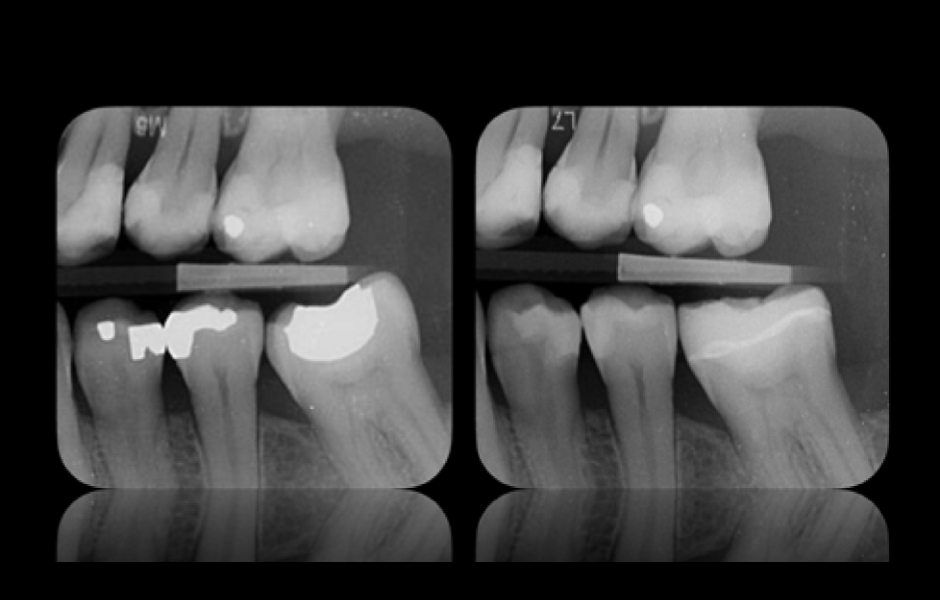

Obr. 12: Radiologické vyšetření. Radiologické snímky (vlevo před a vpravo po) ukazují přesné dosednutí nepřímé rekonstrukce s úplným utěsněním všech marginálních oblastí pryskyřičným cementem, bez přítomnosti přebytků.